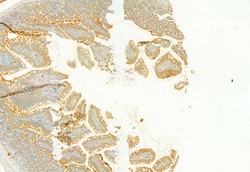

PLCE1 Polyclonal Antibody, Invitrogen™

Antibody detects endogenous levels of total PLCE1.

| Immunocytochemistry, Immunohistochemistry (Paraffin), Western Blot | |

| A synthesized peptide derived from human PLCE1(Accession Q9P212), corresponding to amino acid residues R2267-Q2302. | |